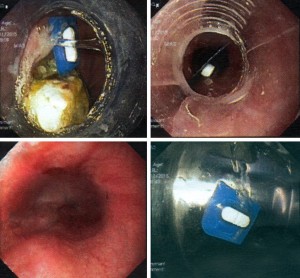

Ngày 01/11/2015 vừa qua, Bệnh Viện Đa Khoa Xuyên Á vừa thực hiện cấp cứu nội soi cho bệnh nhân Nguyễn Thị H, 46 tuổi, ngụ tại xã Tân Phú Trung, huyện Củ Chi, Tp.HCM. Trong khi uống thuốc, do không để ý, chị H. đã quên bóc bỏ vỉ và uống luôn cả vỉ […]